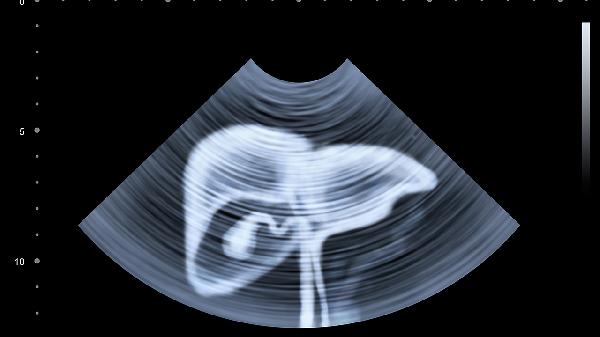

肝囊肿是最常见的肝脏囊性病变,多为先天性胆管发育异常导致。囊壁由单层细胞构成,内含清亮液体。多数患者无自觉症状,常在体检时发现。若囊肿体积超过5厘米或压迫周围组织,可能出现右上腹隐痛、饱胀感。超声检查可明确诊断,无症状小囊肿无须治疗,较大囊肿可考虑超声引导下穿刺抽液或腹腔镜手术。

肝包虫病由细粒棘球绦虫感染引起,牧区多见。囊肿内含有子囊和头节,超声显示特征性"双壁征"或"囊中囊"结构。早期可无症状,后期可能出现过敏反应、胆道梗阻。确诊需结合血清学检查,治疗采用阿苯达唑片联合手术切除,禁用穿刺引流以防扩散。